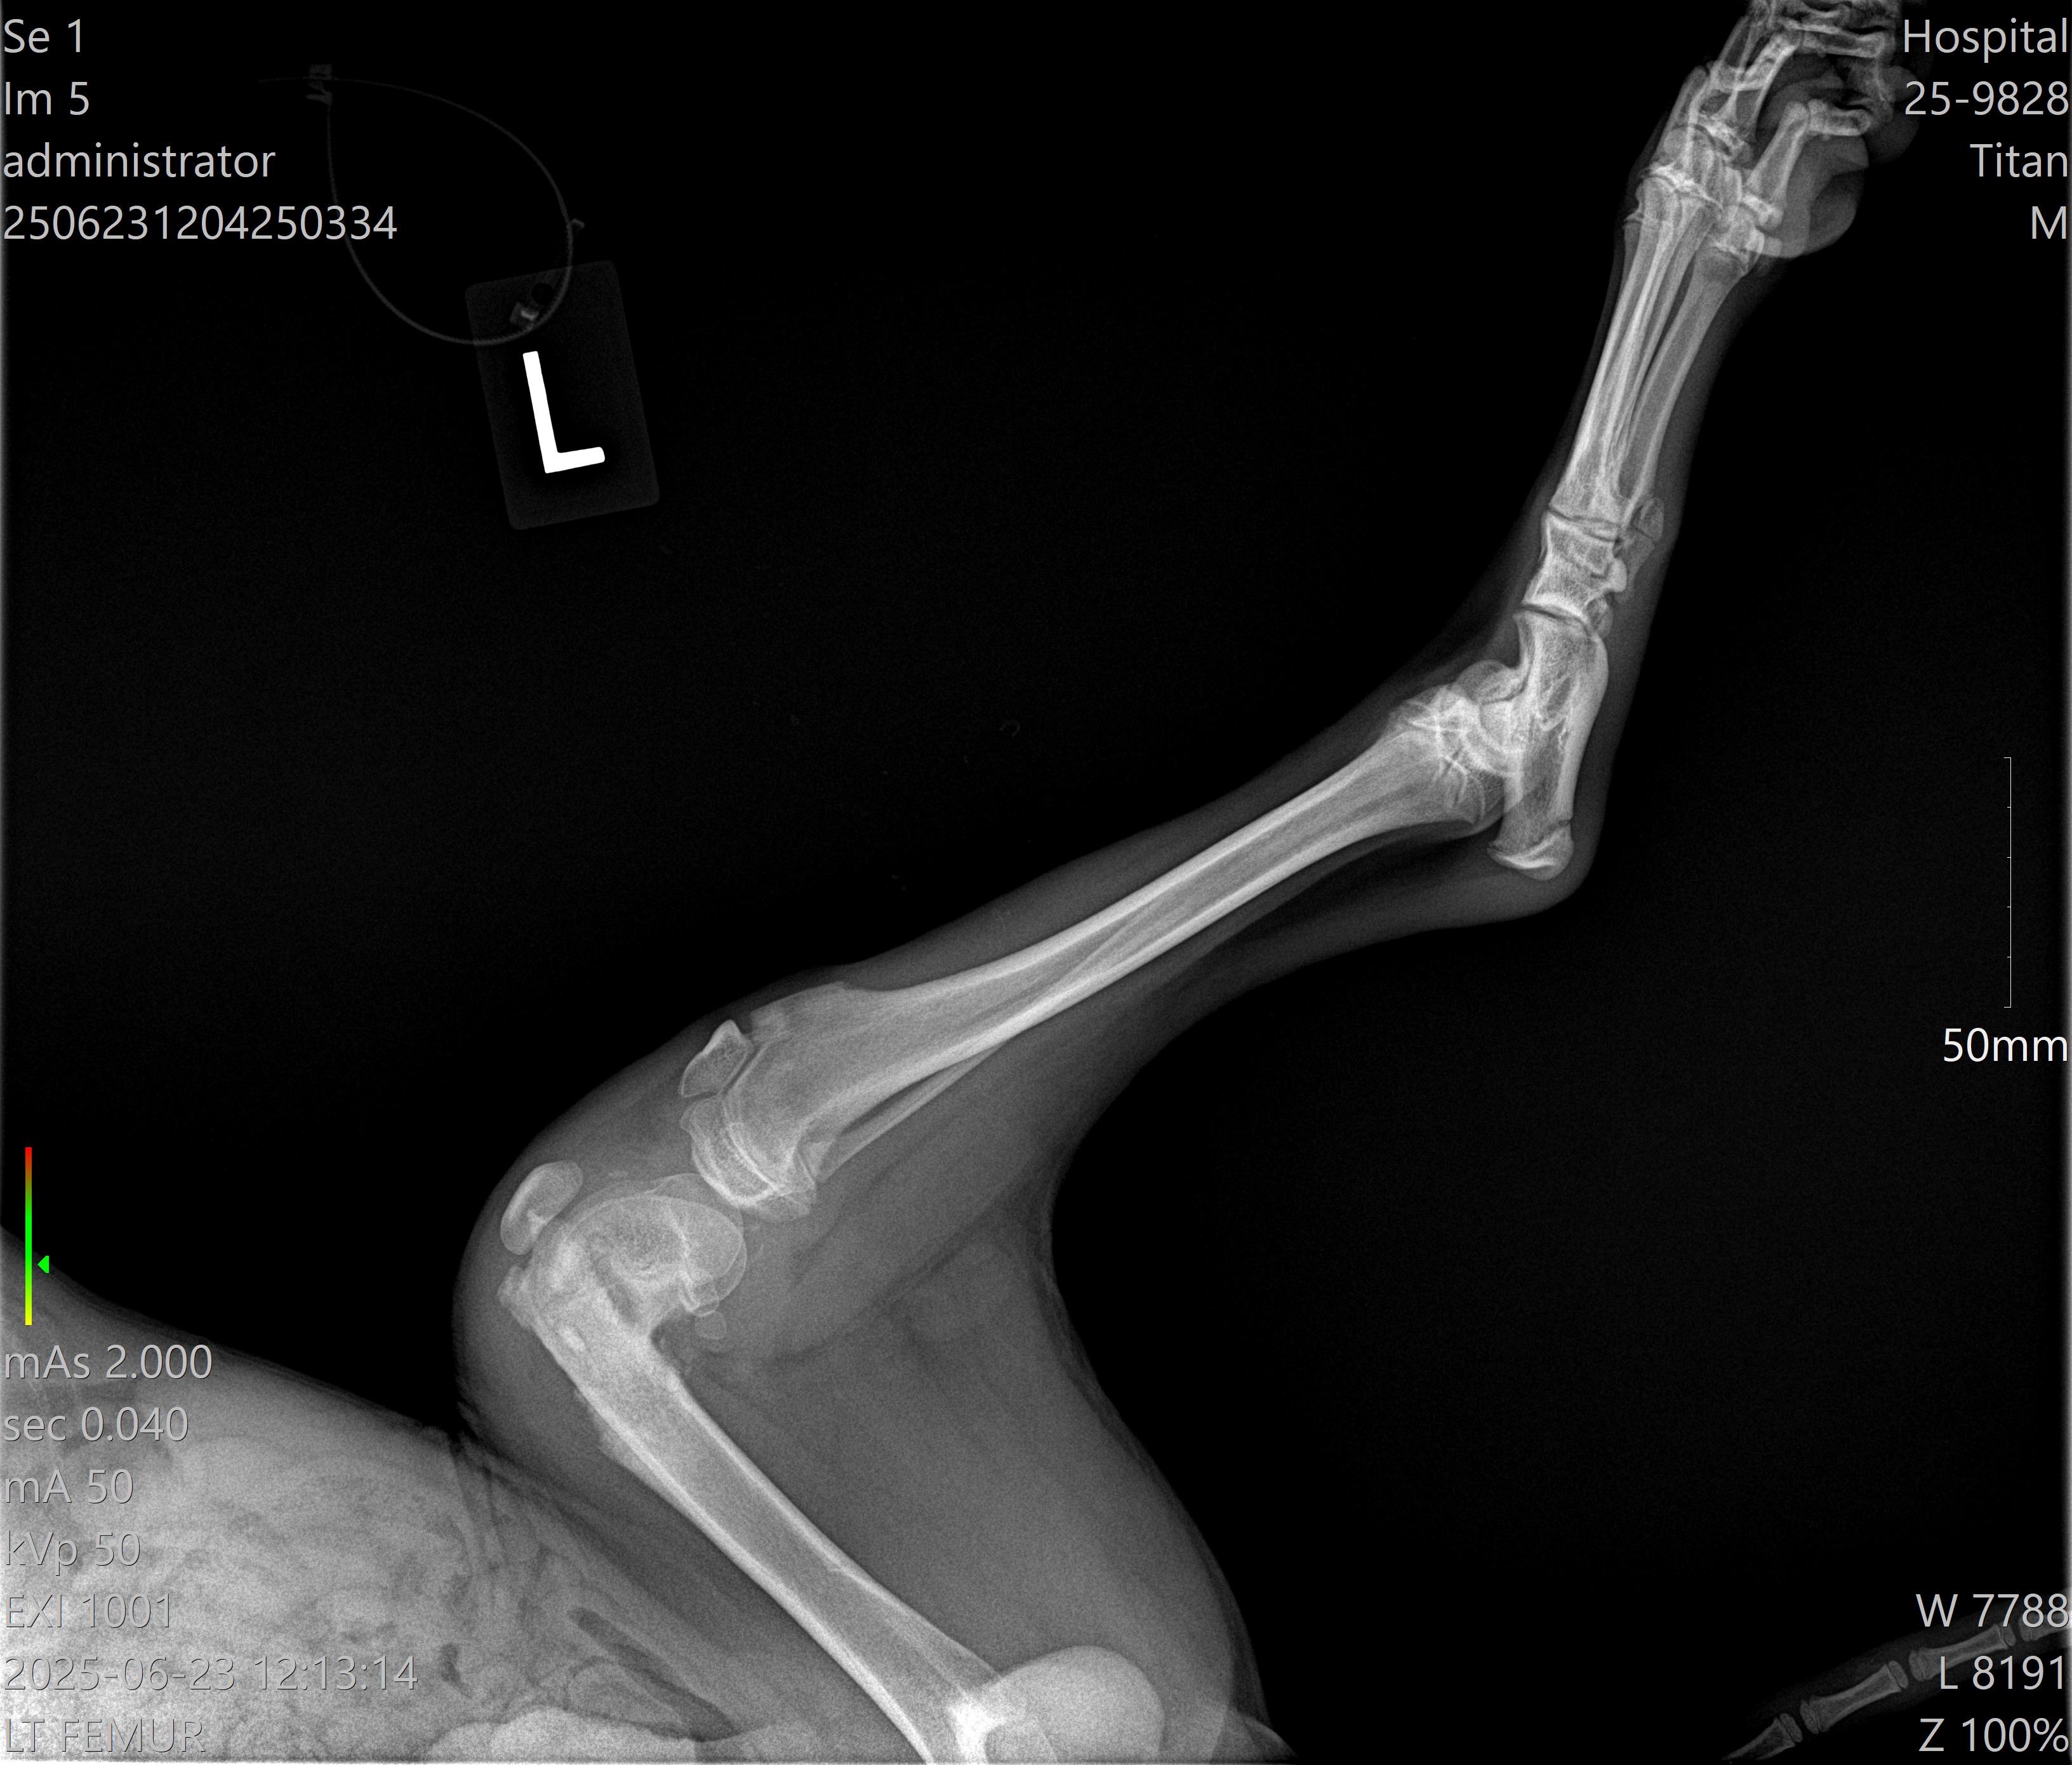

Hello, my name is Makayley! My boyfriend, Mark, and I live in Houston, Texas, and have recently found a very injured puppy. We found him barely able to walk on his back legs, really only using his front two legs to walk. We believe he has been hit by a car. We named him Titan, as we cleaned, fed, and loved him until we were able to take Titan to the vet this morning. The x-rays showed Titan has very bad fractures under both of his back knees. They have been trying to heal themselves, but they are not healing properly. The prognosis for Titan to heal on his own and/or with medication is very low and painful. The vet recommends surgery for each fracture. We do not want to put him down as he is so loving and wants to play with our other three dogs.

We have talked to a surgeon and he has seen both X-rays of Titans legs. He thinks we need to plate both of them. Meaning surgery on both of Titans legs. Please keep sharing and donating! We are so grateful for all of your help